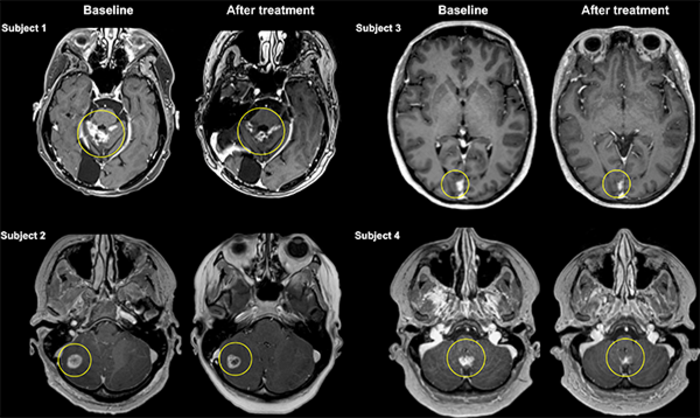

In this Phase I clinical trial for Her2-positive breast cancer patients, the Sunnybrook team captured images of the antibody therapy, trastuzumab (or Herceptin), precisely targeting tumors in the brain after using Insightec’s Exablate Neuro focused ultrasound device to temporarily and noninvasively open the blood-brain barrier (BBB) and enable intravenous trastuzumab to more effectively access tumor sites.

“The early data in this study suggests delivery of antibody therapy directly to tumors using focused ultrasound may impact treatment efficacy, with tumors slightly decreasing in size, with varying results for patients between 7 and 31 percent during the study – on average to 21 percent,” says Dr. Rossanna Pezo, medical oncologist in the Odette Cancer Centre at Sunnybrook. “The reduction in tumor size is promising but should be interpreted with caution as further research on a larger scale is needed.”